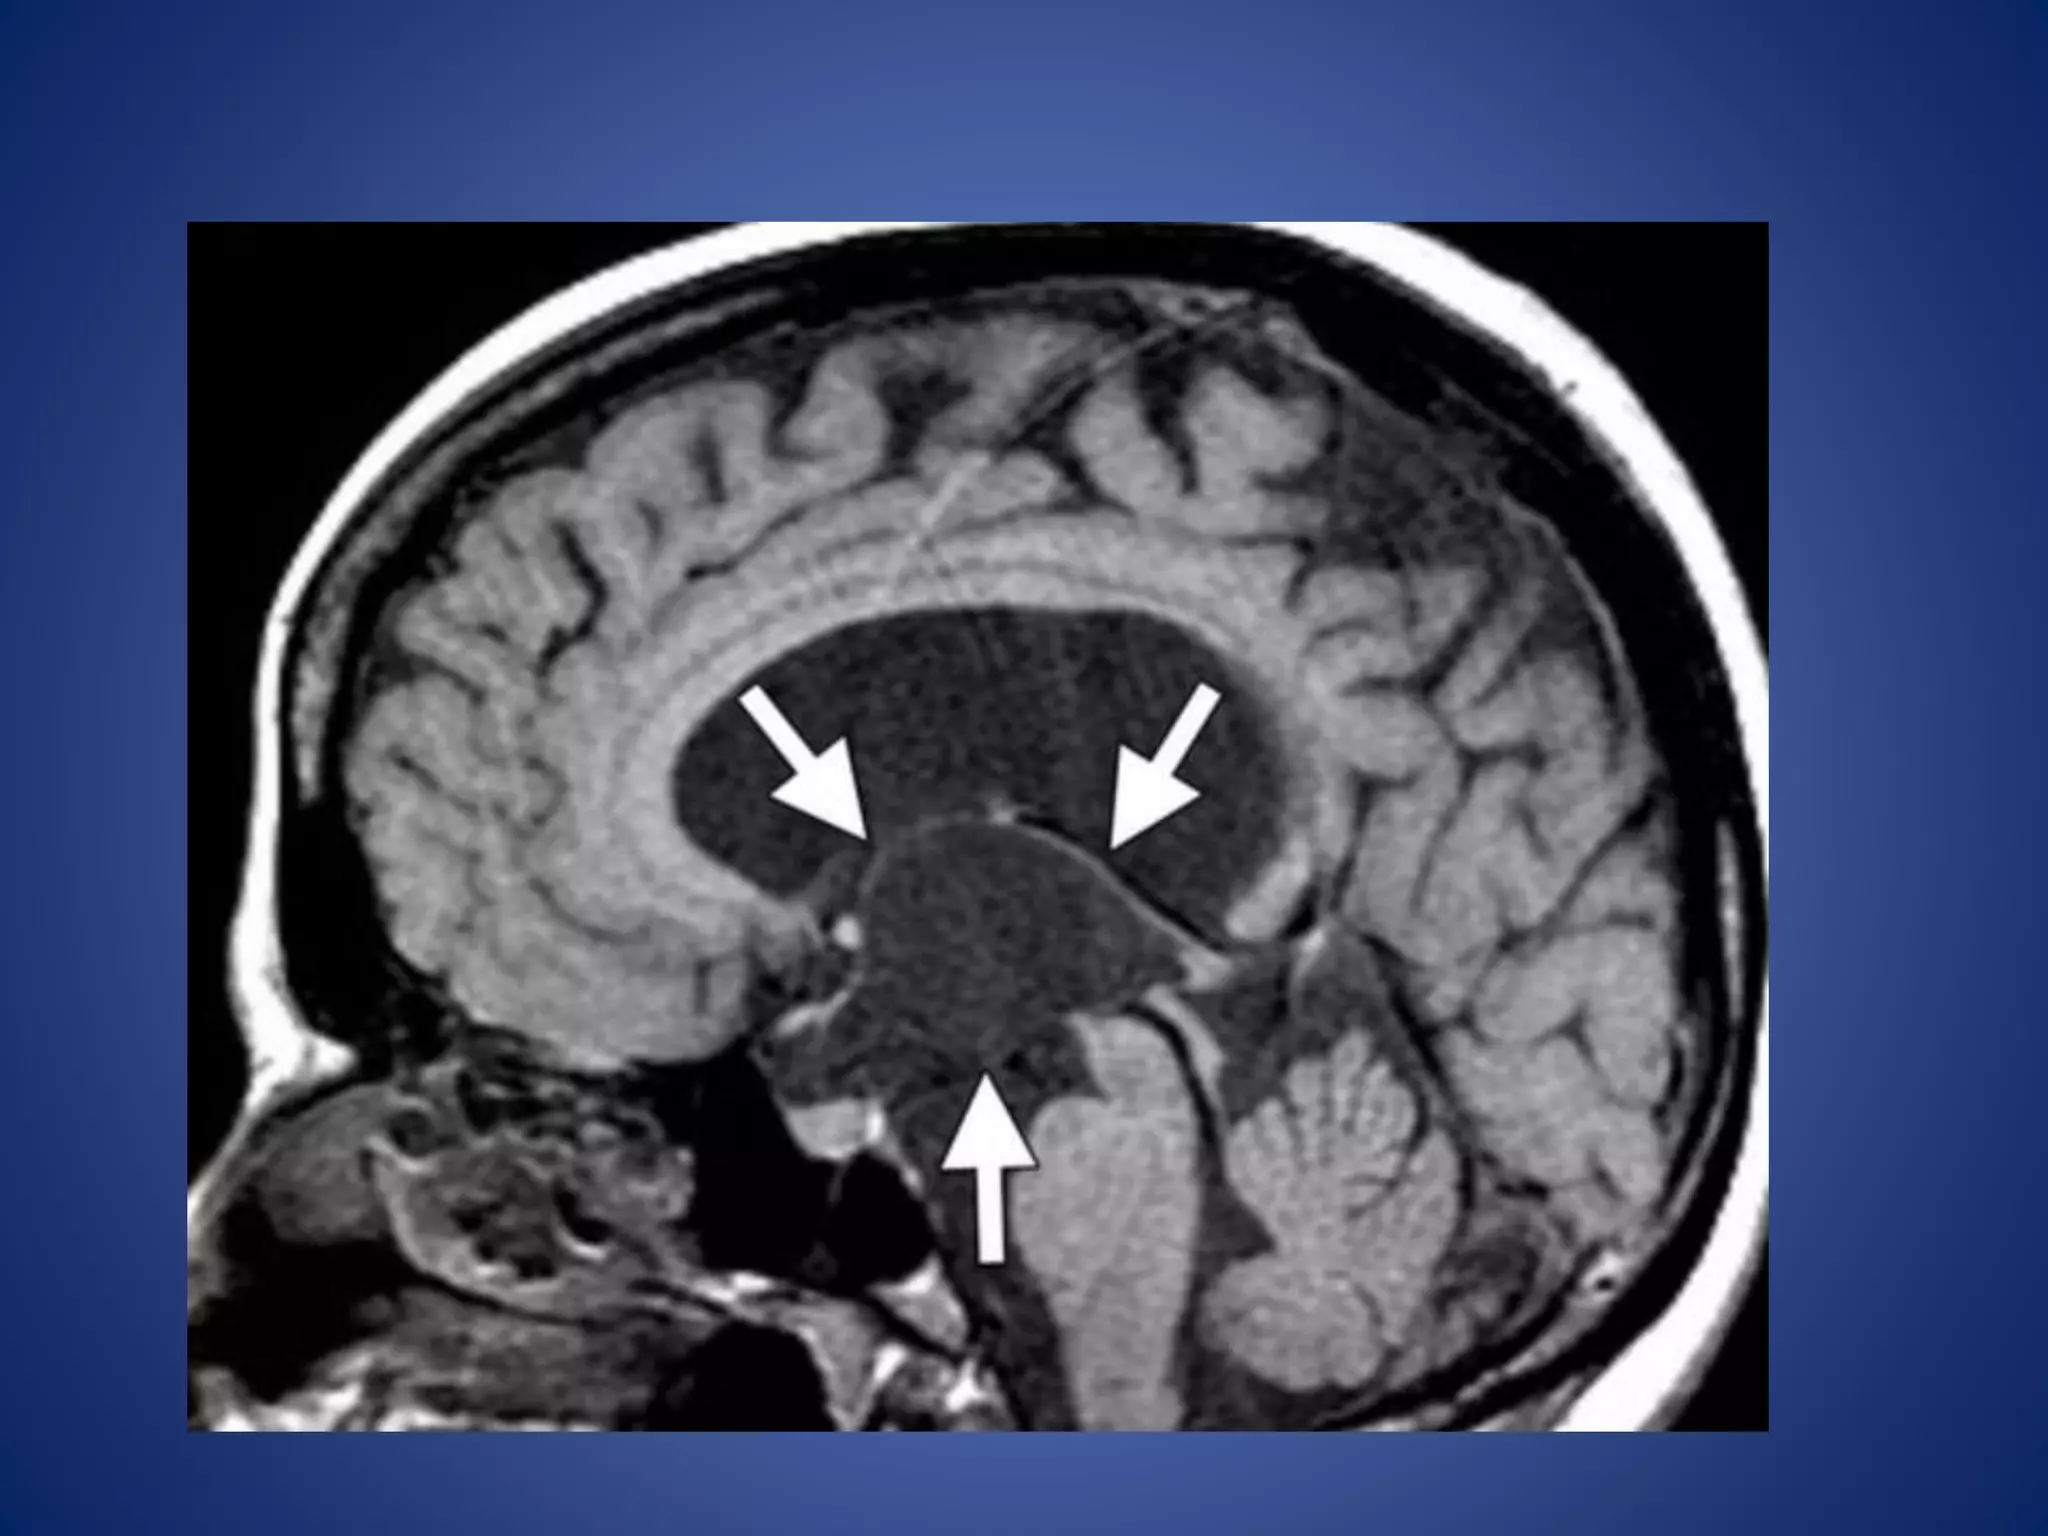

• #24 Suprasellar arachnoid cyst. (a) Midline sagittal T1WI shows a cyst (arrows) that is isointense relative to cerebrospinal fluid.

• #25 (b) Axial T2WI, the cyst (arrows) is homogeneous and isointense relative to cerebrospinal fluid. The lateral ventricles (*) are dilated due to obstruction by the cyst.

• #26 the cyst (arrows) demonstrates no enhancement

Hypothalamic Hamartoma

Hypothalamic hamartoma is the lesion most commonly associated

with CPP, being implicated in up to 60% of cases.

Hypothalamic hamartomas may be either

• sessile (intrahypothalamic) or

• pedunculated (parahypothalamic).

Imaging Features.—

Sessile hypothalamic hamartomas may expand the hypothalamus.

Pedunculated hypothalamic hamartomas usually arise from the

floor of the hypothalamus and extend inferiorly.

They are typically isointense relative to gray matter with T1- and

T2-weighted sequences, although they may be mildly hyper- or

hypointense relative to gray matter with T2-weighted sequences